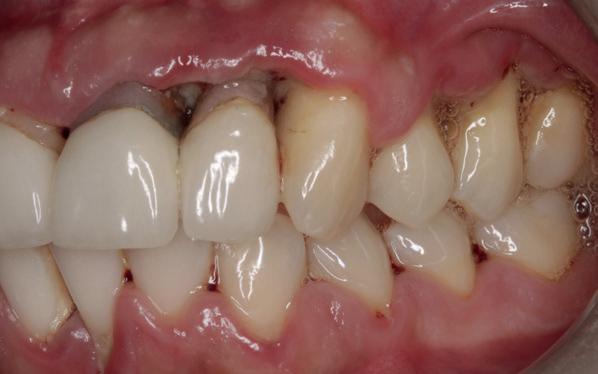

De patiënt, een 70-jarige man, had in het verleden tandheelkundige zorg ontvangen die zich kenmerkte door een ad hoc benadering. Er was geen sprake van een overkoepelend behandelplan of lange termijnvisie. De patiënt had naar eigen zeggen jarenlang niets

1. Studiofoto intake

aan zijn gebit gedaan behalve pappen en nathouden. Tandheelkundige zorg werd enkel verleend wanneer er zich een probleem voordeed (afbeelding 1, 3, 5).

De patiënt werd in de eerste fase gezien door de parodontoloog, implantoloog en restauratief behandelaar. Klinisch werden drie complicerende factoren vastgesteld: inadequate mondhygiëne, een ongunstige occlusale relatie en restauraties met gebrekkige marginale adaptatie met overhang. De patiënt werd opgenomen in het parodontale behandelprotocol.

De diagnose luidde lokaal parodontitis met ernstige furcatie aandoeningen; Stadium IV (vergevorderd); graad C (snel progressief) (afbeelding 7) De elementen die niet te behouden waren, werden geëxtraheerd.

Na afronding van de eerste twee behandelstappen werd parodontale stabiliteit bereikt, zoals waarneembaar op de parodontiumstatus en (röntgen)foto’s (afbeelding 6, 8). De patiënt toonde aantoonbare verbetering in mondhygiëne (afbeelding 4) en bleef gemotiveerd om de behandeling voort te zetten.

3. Lichtfoto intake

4. Lichtfoto na infectie controle